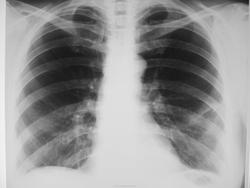

Сегодняшние снимки

img_2738.jpgimg_2739.jpg

Миргалина wrote:

Ну, а Вы боялись. Так есть динамика, а? Так-то, друзья!

Так может начинаться центральный рак. Мало того, изменения могут исчезать на фоне противовоспалительной терапии. А потом появляться вновь.

Дисковидный ателектаз расправился, инфильтрации как не было, так и нет.